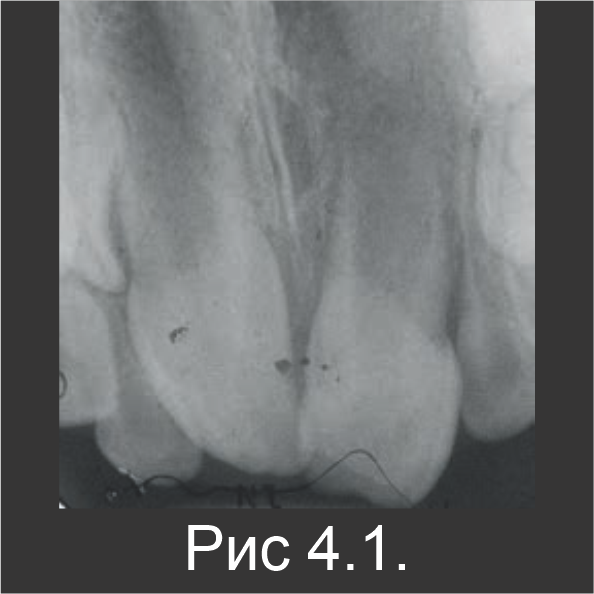

6-летнего мальчика направили на лечение абсцесса зуба № 21. За две недели до этого он перенес травму зуба. У него был диагностирован неосложненный перелом коронки зуба 21. У него была болезненная припухлость со щечной стороны от зуба 21, и во время пальпации из бороздки выделялся гной. При этом пульпа была закрыта. Зуб имел увеличенную подвижность и был чувствительным к перкуссии. При контакте с холодовым раздражителем реакции не наблюдалось, что позволило предположить полный некроз пульпы. На рентгенограмме был обнаружен совсем незрелый резец 21 с просветлением в области апекса, которое имеет большое значение (рис. 4.1).